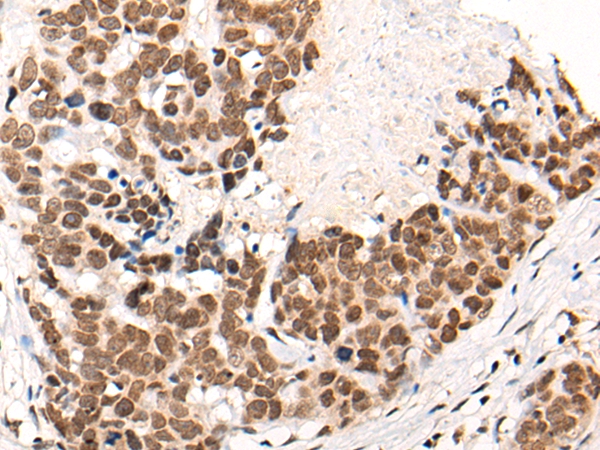

![CACNA1H Antibody[46383]](https://img1.dxycdn.com/p/s14/2025/0923/226/0299446280695040791.jpg)

The image on the left is immunohistochemistry of paraffin-embedded Human thyroid cancer tissue using 46383(CACNA1H Antibody) at dilution 1/40, on the right is treated with synthetic peptide. (Original magnification: x200)

![CACNA1H Antibody[46383]](https://img1.dxycdn.com/p/s14/2025/0923/022/8290895430695040791.jpg)

The image on the left is immunohistochemistry of paraffin-embedded Human ovarian cancer tissue using 46383(CACNA1H Antibody) at dilution 1/40, on the right is treated with synthetic peptide. (Original magnification: x200)